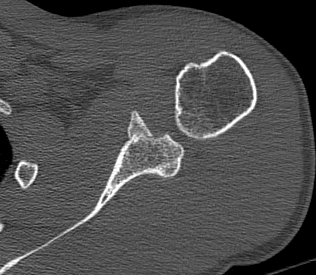

Combined Glenoid and Scapula Fractures

Case 1

- displaced glenoid fracture and neck fracture

- ORIF both through posterior / Judet approach